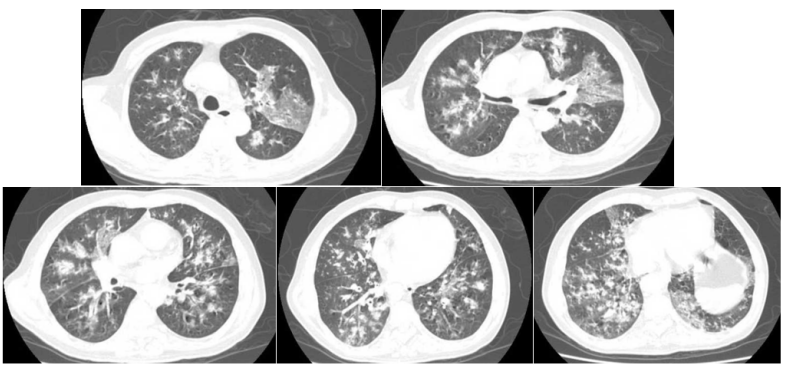

IAPA在发展过程中,较早可出现咳嗽、咳痰,进而出现呼吸困难、呼吸衰竭、缺氧性ARDS,进展迅速,即使气管插管、建立人工气道,患者也常出现气道峰压逐渐升高、潮气量逐渐下降,常因呼吸衰竭而无法挽救。但因其临床表现不特异,导致早期识别存在一定困难。(1)气管-支气管侵袭征象:沿支气管分布的结节及斑片影。对于没有基础疾病的重症流感病毒性肺炎患者,粒细胞数量正常,在曲霉感染后肺组织内会出现白细胞介导的强烈的炎症反应,导致渗出性支气管炎、支气管或肺泡受损及出血坏死,但直接侵袭血管的曲霉丝较少且主要以非增殖状态存在,因此多出现弥漫全肺的非特异性气道受侵型表现,而血管受侵型表现少见。如下图所示,第1天,支气管壁似乎有轻度增厚。病情进展至第4天,支气管壁明显增厚。随后迅速发展为支气管周围炎,并沿支气管侵袭、播散。图源:Respirol Case Rep, 2016, 4(1):32-34.注:双下肺实变,沿支气管血管束分布的实变、空洞,斑片状渗出影。注:支气管壁增厚、树芽征和沿着支气管血管束分布的实变。(2)对于免疫抑制宿主,可出现典型的曲霉感染影像学表现,例如实变与空洞伴晕征、空洞内有丝状结构及悬浮结节。注: A图见多叶肺炎和严重的小叶中心性、节旁性肺气肿; B图见右肺中叶空洞性浸润, 右肺下叶致密实变。图源:Chest, 2021, 160(2):e181-e184.注:A图可见实变、空洞,空洞内见丝状结构及悬浮结节;B图可见空洞、空气新月征。IAPA一种特殊的类型——侵袭性气管支气管炎,在支气管镜直视下可见气管和/或支气管溃疡、斑块或结节、假膜,是其典型表现。图源:国际呼吸杂志, 2023, 43(4):448-453.肺活检组织、气道斑块、假膜或溃疡的活检/刷检标本中发现真菌菌丝等特征性病理表现,可作为确诊标准。此外,在痰、支气管抽吸物、支气管肺泡灌洗液(BALF)中找到曲霉菌丝也可作为临床诊断标准。图源:Lancet Respir Med, 2018, 6(10):782-792.注:支气管活检组织病理显示有坏死物质和真菌成分,菌丝呈分枝状。图源:Chest, 2021, 160(2):e181-e184.图源:Tuberc Respir Dis (Seoul), 2014, 77(3):141-144.半乳甘露聚糖(galactomannan,GM)是曲霉特有的细胞壁多糖成分。菌丝生长时,半乳甘露聚糖是最早释放的抗原,是早期检测曲霉感染的经典方法。主要包括血清GM试验和BALF GM试验。血清GM试验在非粒细胞缺乏患者敏感性较低,仅为50%左右;ICU IPA患者的血清GM试验敏感性仅为30%~50%。在IAPA患者中,当以0.5作为GM试验阳性阈值时,诊断率仅20%。对于非中性粒细胞减少患者,BALF GM试验比血清GM试验具有更高的IPA诊断效率。EORTC/MSG标准采用1.0作为单份BALF阳性阈值的标准,当同时联合血浆/血清GM试验阳性时,BALF标本阈值可下调至0.8。我国学者研究发现,当截断值从0.5增加到0.717时,BALF GM试验可以显著降低假阳性率。无论是2016年美国传染病学会(IDSA)发表的《曲霉病诊断和管理实践指南》,还是2017年欧洲临床微生物学和感染病学会(ESCMID)/欧洲医学真菌学联盟(ECMM)/欧洲呼吸学会(ERS)联合发表的《曲霉病的诊断和管理指南》,都提及血清曲霉特异性IgG抗体在慢性肺曲霉病中有最高的检测阳性率。但2023年Clin Microbiol Infect杂志发表的一篇文章显示,IPA组的曲霉IgG抗体水平明显高于非IPA组。采样时间为发病后1~3个月内亚组显著高于采样时间为发病后<1个月亚组,影像学出现肺部空洞性病变亚组显著高于非肺部空洞性病变亚组。经过对比发现,曲霉IgG抗体的特异性和阳性预测值显著低于BALF GM。PCR的优势在于不仅能检测出曲霉的属和种,还可通过识别CYP51A基因突变来判断是否存在三唑类耐药可能。标本选择顺序:BALF>血浆>血清,但已进行了抗真菌治疗患者的血样本PCR阳性预测值可从62%降至5%。单份PCR阴性结果可极大程度地排除IPA可能。PCR可能更适合用于可疑IAPA患者在拟行抗真菌治疗前的筛查以及治疗过程中的实时监测。mNGS优势在于覆盖能力广, 时效性好, 不受先前使用抗菌药物的影响, 并可提供病原鉴定分型、耐药基因及毒力因子分析。但其检测成本较高, 结果需要临床医生进行解读和判断, 标本选择以BALF为最佳。